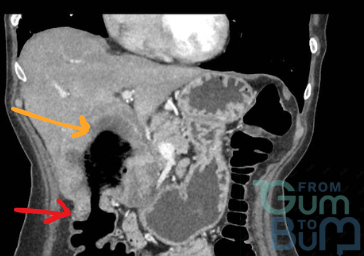

Male 60 yo, presented with dull aching intermittent pain in RUQ for 6 weeks. No fever or diarrhoea. Liver blood test showed ALT of 70 U/L, ALP 150 U/L, rest normal.  FBC showed neutrophilia.

Patient is retired for the last 5 years but used to own a dog rescue shelter. Drinks in excess about 25 units a week since retired. AFP and Ca 19,9 were normal. Serology for Entamoeba histolytica and Echinococcus were equivocal.

What next?

Click the image to see the answer >

Hydatid cyst type II: central cyst with daughter cyst(s). 10% can be seronegative. Key is contact with possible animal hosts (Dog or sheep), incubation period is often years.Amebiasis usually has a preceding history of diarrhoea and fecal-oral transmission. Albendazole 400 mg BD 4 weeks and given cyst is >5cm, consider PAIR therapy. Repeat serology (fluid aspiration has risk of rupture/ anaphylaxis (too risky just for diagnosis)